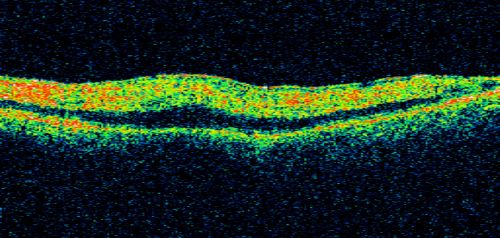

80 Year old man with 3 day history of vision loss right eye. Vision 4/200.

CRAO - 3 days old - plaque in vessels